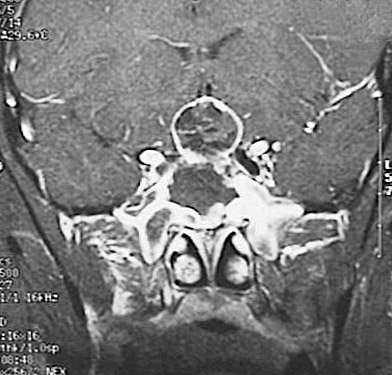

Click on the craniopharyngioma in the MRI scan above:

This MRI scan demonstrates an expanding mass with irregular margins in the suprasellar region.